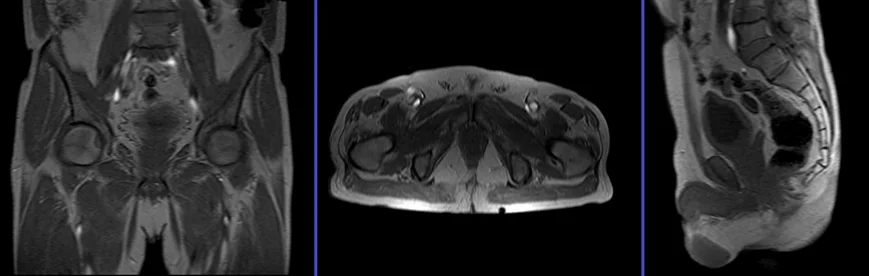

pause for proctogram

Next, guide the patient to lie down in either a right or left lateral position. The radiologist will gently insert a small catheter lubricated with ky jelly into the rectum and inject a small amount of sonography gel. Afterward, remove the catheter and place the patient back into the initial position. Instruct the patient to clench, relax, and strain during image capture.

T2 TRUFISP cine, small FOV 10mm, 1 second, 150 measurements.

Plan the sagittal slices on the axial plane; angle the positioning block parallel to the interpubic fibrocartilage and the anal canal. Check the positioning block in the other two planes. An appropriate angle must be given in the coronal plane (parallel to the rectum and the anal canal). Slice must be positioned over the middle of the rectum and anal canal.

After approximately five measurements, instruct the patient to strain and expel the gel from the rectum onto the incopads beneath, while ensuring that cine scans are continuously running during this process.